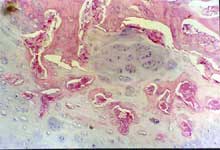

2周软骨岛                              骨断端无骨痂

4周软骨钙化                            骨小梁形成